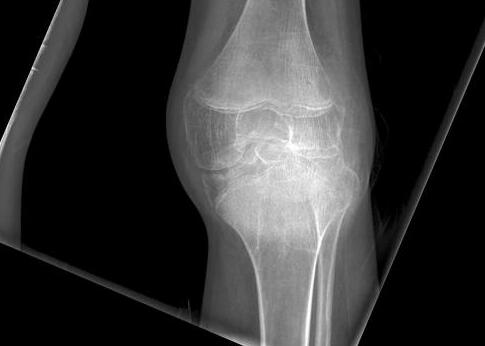

在膝、髋等较大关节的X线表现主要是软骨混浊,此乃由于软骨钙化或铁质沉积之故。